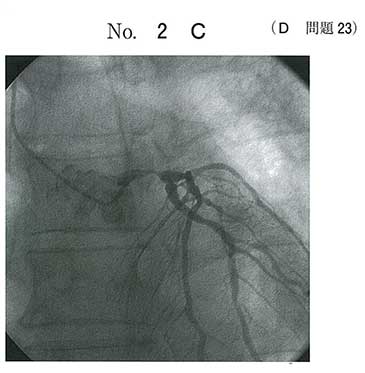

uAP患者

LMT及びRCAに狭窄あり。PCIは無理

3本狭窄 a

右冠動脈と左冠動脈本幹の狭窄だと思います。

バイパス術の適応。

AVR誘導のST上昇は左主幹部病変をまず考える